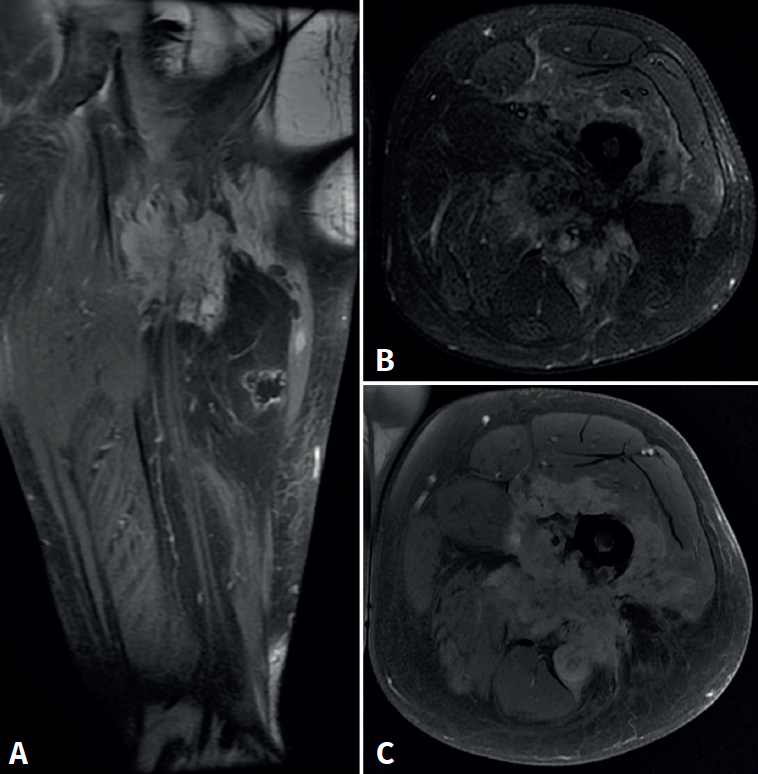

Se trata de un varón de 57 años, empleado en recogida de basura. Diez días antes de la consulta sufre una caída accidental con dolor intenso en el miembro inferior izquierdo, hipoestesia en calcetín y debilidad para la flexión y extensión del tobillo. En la exploración física presentaba Lasègue izquierdo negativo, derecho positivo a 50° y femoral stretch test derecho positivo. Se constató fuerza 1/5 en el tobillo izquierdo. La resonancia magnética (Figura 1) mostró discopatía L4-L5 con hernia discal posteromedial derecha. La electromiografía (EMG) evidenció afectación radiculoplexular izquierda moderada L3-L4 y grave L5-S1 posganglionar.

Figura 1. Resonancia magnética lumbar inicial. A: corte sagital en secuencia T2: discopatía de grado IV en L4-L5 con hernia discal extruida; B: corte axial en secuencia T1 a nivel de L4-L5, con estenosis del receso lateral derecho secundaria a extrusión discal; C: corte axial en secuencia T2, con protrusión discal difusa con estenosis foraminal bilateral y canal medular estrecho (grado C según Schizas-Theumann).